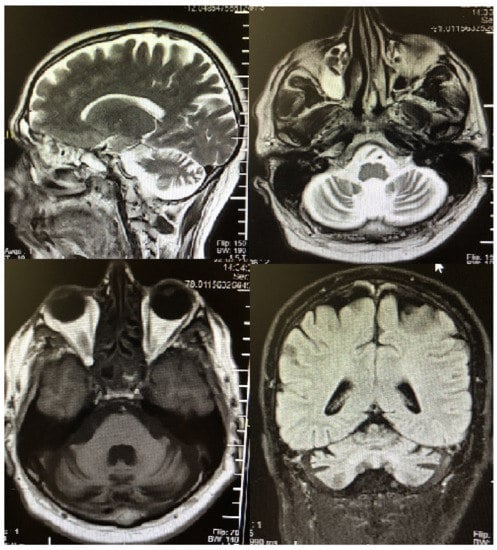

2. Case Description